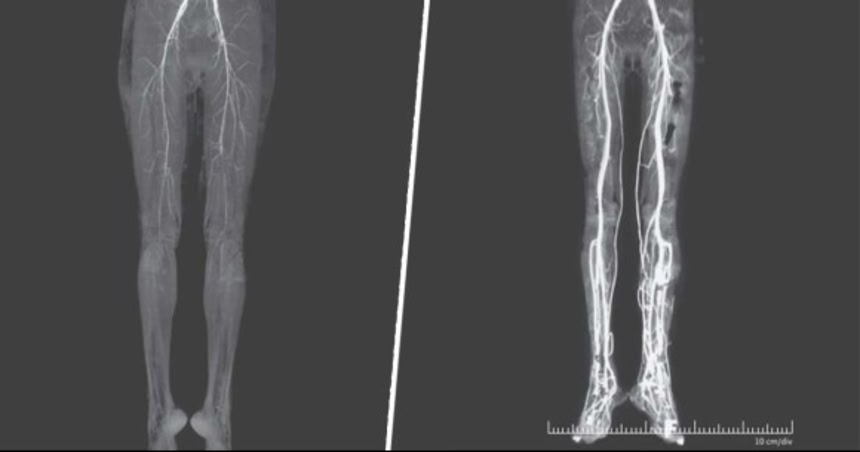

CT検査の結果、女性の脚は下肢に血液を供給する役割を果たす膝窩動脈と背側中足動脈という2つの動脈の幅が極端に狭くなっていることから血液が凝固し、循環していなかったことがわかった。